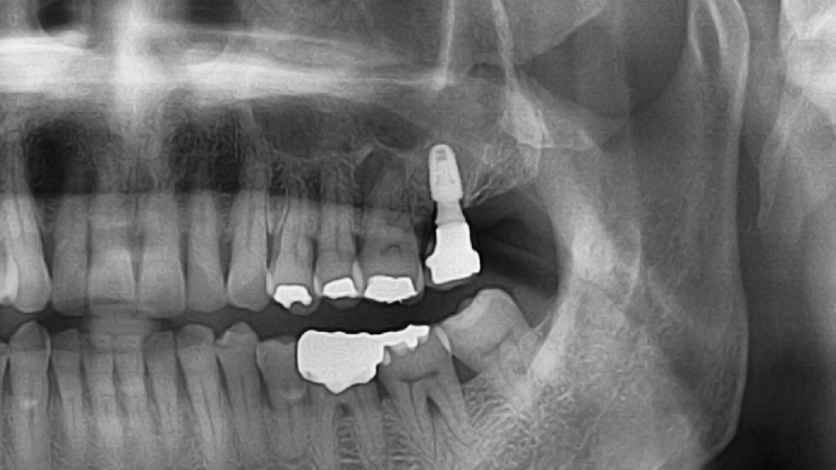

Clinical Cases

Video